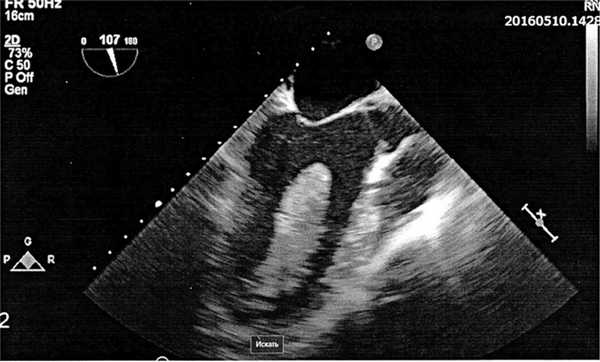

При чреспищеводной эхокардиографии (ЧПЭхоКГ) (рис. 1) выявлено гиперэхогенное объемное образование (тромб разной степени организованности) размером 2,0×7,4 см в полости ЛЖ, исходившее из его верхушки на широком основании. Новообразование имело продолговатую форму, фестончатые края, располагаясь вдоль полости ЛЖ, занимало 35—40% его объема; отмечалась умеренная флотация тромба в проекции его верхней части. От передней поверхности объемного образования отходили плотные фиброзные тяжи к межжелудочковой перегородке (МЖП). Его верхний полюс был расположен в 1,6—1,8 см от створок аортального клапана (АК), а передняя створка митрального клапана (МК) в диастолу соприкасалась с его верхней флотирующей частью. Обращали внимание: закругление и расширение верхушки ЛЖ, выраженный диффузный гипокинез; в области МЖП и передней стенки ЛЖ — гипо- и акинез. Конечный диастолический объем (КДО) ЛЖ — 195 мл, конечный систолический объем (КСО) ЛЖ — 135 мл, фракция изгнания (ФИ) ЛЖ — 25,8%.

Рис. 1. Чреспищеводная ЭхоКГ больного А., 43 лет. Диагноз: объемное образование (тромб) левого желудочка.